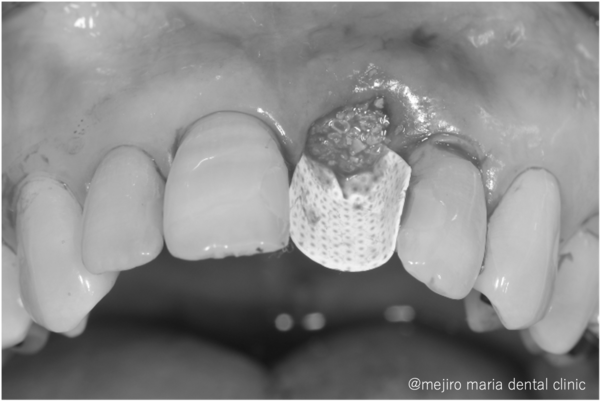

左側中切歯を抜歯し、抜いた穴の中を徹底的に綺麗にします。その後、骨の吸収を抑えるために人工骨を填入し、PTFEメンブレンという人工の膜でカバーし、縫合します。

丁寧で愛護的な抜歯と、適切な材料をチョイスすることで、術後の骨と歯茎のボリュームダウンを極力防ぐことができます。